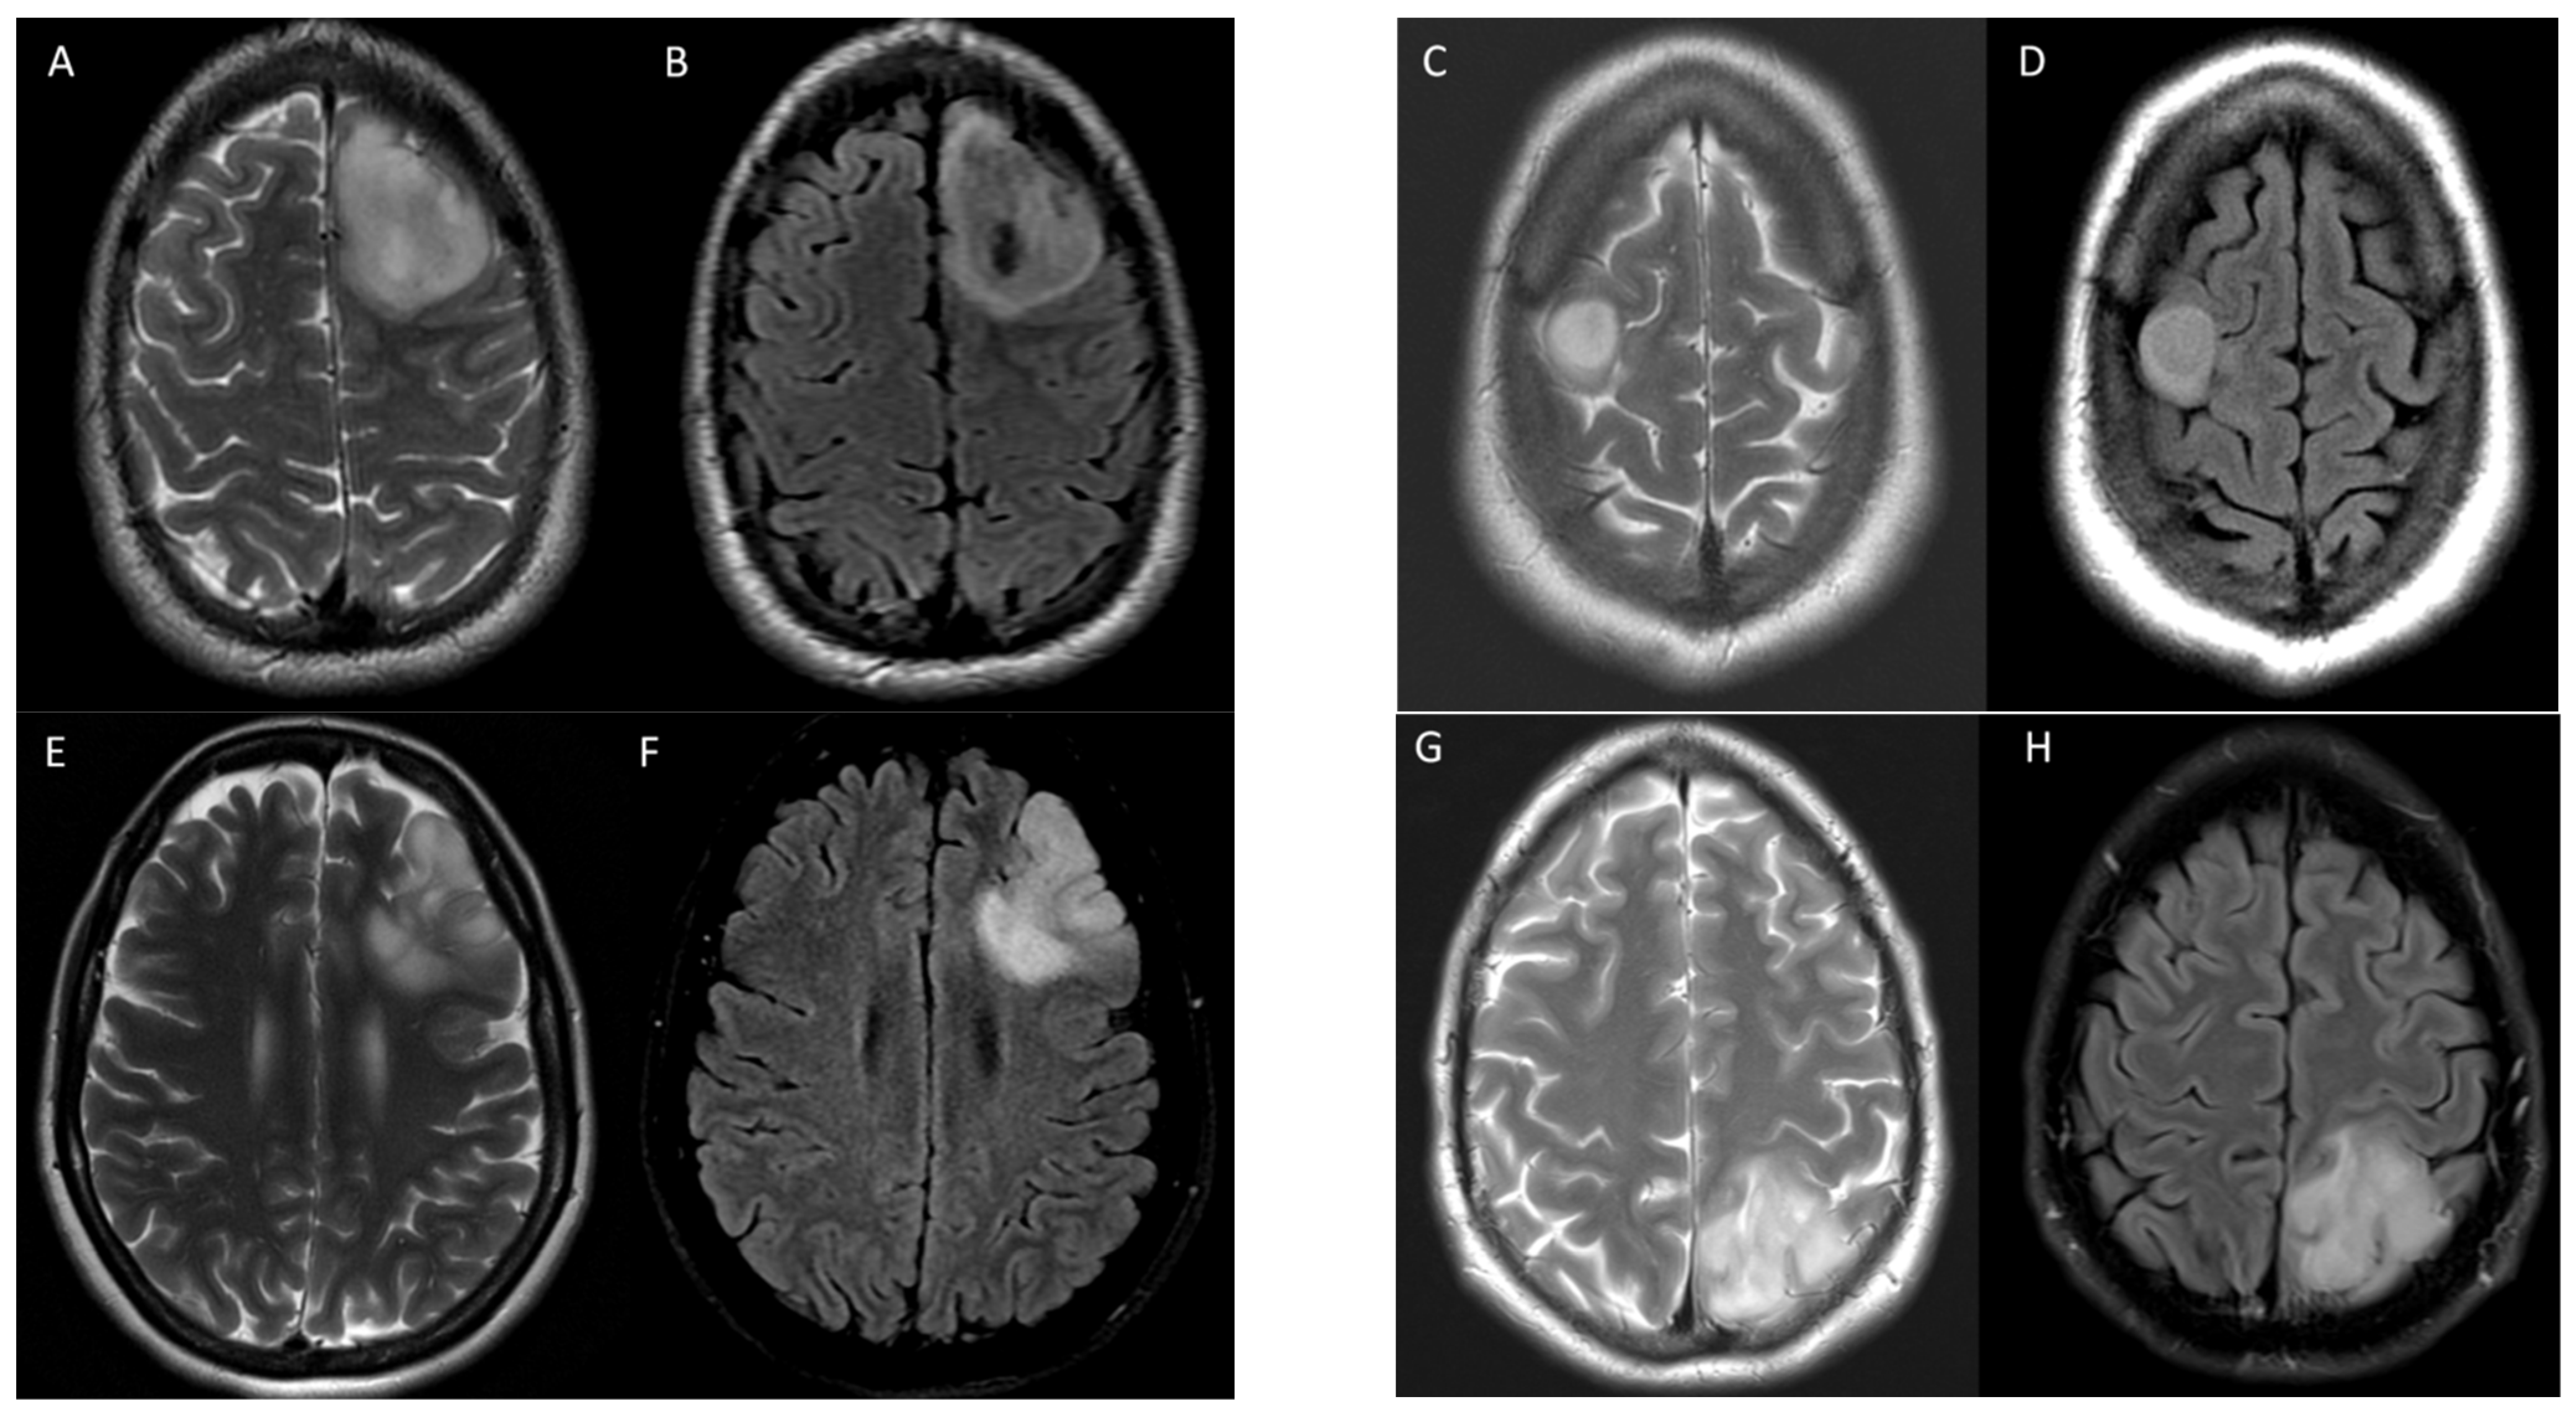

2.3. Image Analysis

3.2. T2-FLAIR-Mismatch-Based Prediction of 1p/19q Co-Deletion Status

3.3. Radiomic-Based Prediction of 1p/19q Co-Deletion Status